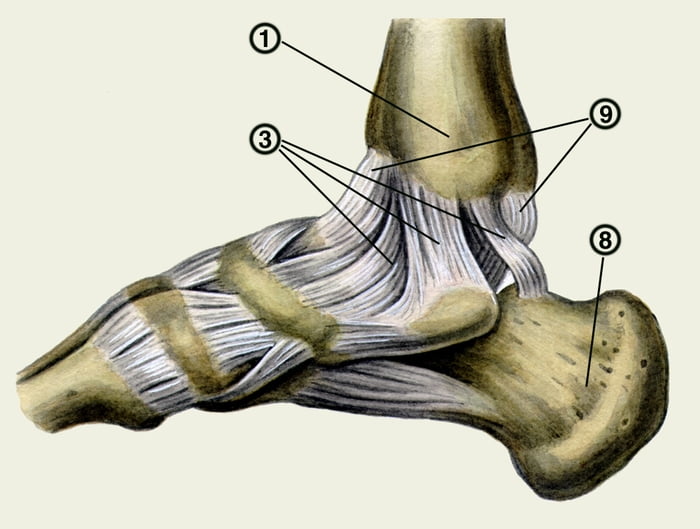

Анатомические фото голеностопного сустава и его суставных поверхностей